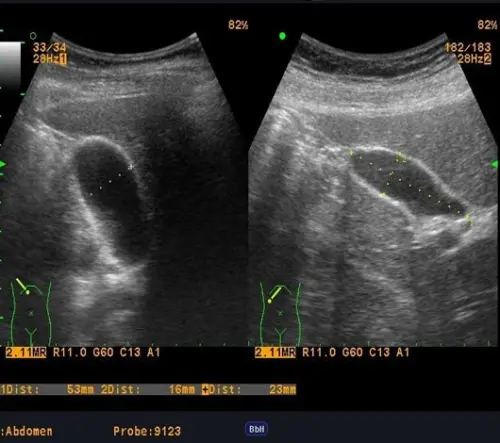

УЗИ брюшной полости (УЗИ ОБП) – это безопасный и информативный метод диагностики. Исследование позволяет оценить состояние внутренних органов с помощью ультразвуковых волн, как радар в океане человеческого тела. Это комплексное исследование, которое включает УЗИ печени и желчного пузыря, УЗИ поджелудочной железы, УЗИ селезенки и других органов.

Процедура не имеет противопоказаний и не вызывает болевых ощущений. В процессе ультразвуковой диагностики врач получает изображение органов в режиме реального времени, что позволяет оценить не только их структуру, но и функциональность. При необходимости может быть проведено УЗИ брюшной полости с допплером для детальной проверки внутренних органов и их кровоснабжения.

Экспертное УЗИ брюшной полости позволяет врачу "заглянуть" внутрь организма без инвазивных вмешательств:

- Оценить размеры, форму и структуру органов, включая печень, поджелудочную железу, селезенку и почки

- Выявить новообразования, воспаления, сосудистые патологии при проверке внутренних органов

- Диагностировать желчнокаменную болезнь и кисты при диагностике ЖКТ на УЗИ

- изучает их структуру и эхогенность

- проверяет наличие новообразований